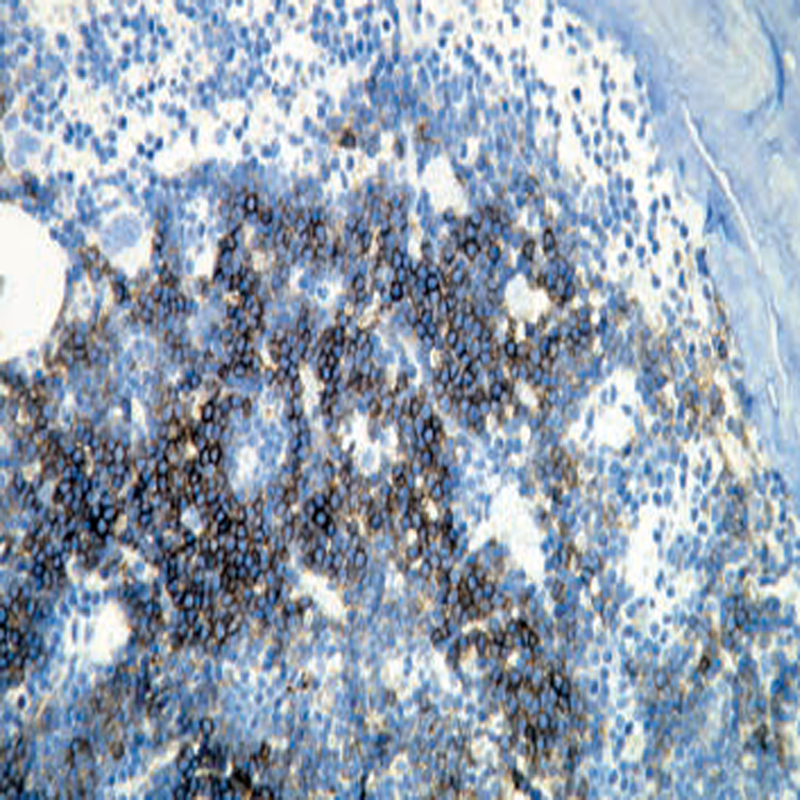

Immunohisto Chemistry

IHC Products